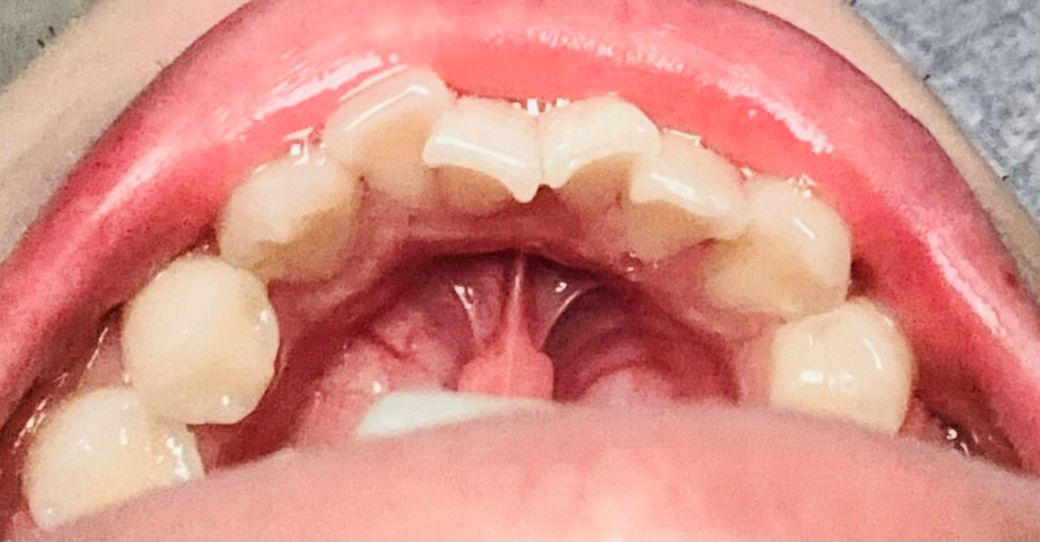

아래 앞니 안쪽 잇몸 퇴축이 심한 편인가요?

아래 앞니 안쪽에 잇몸 퇴축이 심한편인가요? 안쪽 양치질 방법은 세로로 세워서 왔다갔다 반복하는데 제가 생각하기로는 칫솔을 세워서 왔다 갔다 거리면 칫솔이 잇몸을 늘리게 하는것 같아서 걱정됩니다

위쪽에서 찍은 사진보다는 정면에서 찍은 사진이 잇몸퇴축이 더욱 잘 보입니다.

이사진 상으로는 그다지 잇몸이 퇴축된 것은 아닙니다.

• 현재 사진상으로는 잇몸 퇴축이 심해보이지 않으며, 잇몸 손상을 막기 위해 부드러운 칫솔모로 반복적으로 문질러 양치를 하여 주길 권합니다.

• 사진으로는 잇몸 퇴축의 정도를 확인하기 힘들어 보입니다 잇몸 퇴축은 일반적으로 양치질을 너무 세게 해서 자극으로 인해서 생기거나 치아에 가해지는 힘이 과할 때 생깁니다 양치질을 할 때 치아가 난 방향으로 부드럽게 양치질을 해주는 것을 권유 드립니다

• 현재 사진으로는 잇몸 퇴축 정도를 정확히 판단하기 어렵지만 심한 정도는 아닙니다. 다만 정확한 판단을 위해서는 probe를 통한 잇몸 검사 그리고 x-ray 등의 촬영이 필요합니다.

• 안녕하세요 치과의사 김철진입니다. 사진상으로 보면 잇몸퇴축이 심한거 같진 않습니다. 하지만 치열이 좋지 않아서 치아에 힘이 많이 가해지면 잇몸이 퇴축될수 잇으니 관리를 잘해주시는게 중요할것같습니다.

1. 사진상 보이기에는 해당 부위 치은퇴축이 아주 심하진 않습니다.

2. 칫솔질 방법은 세로 방향으로 왔다갔다 하는 것이 잇몸 퇴축 방지에 도움이 됩니다.